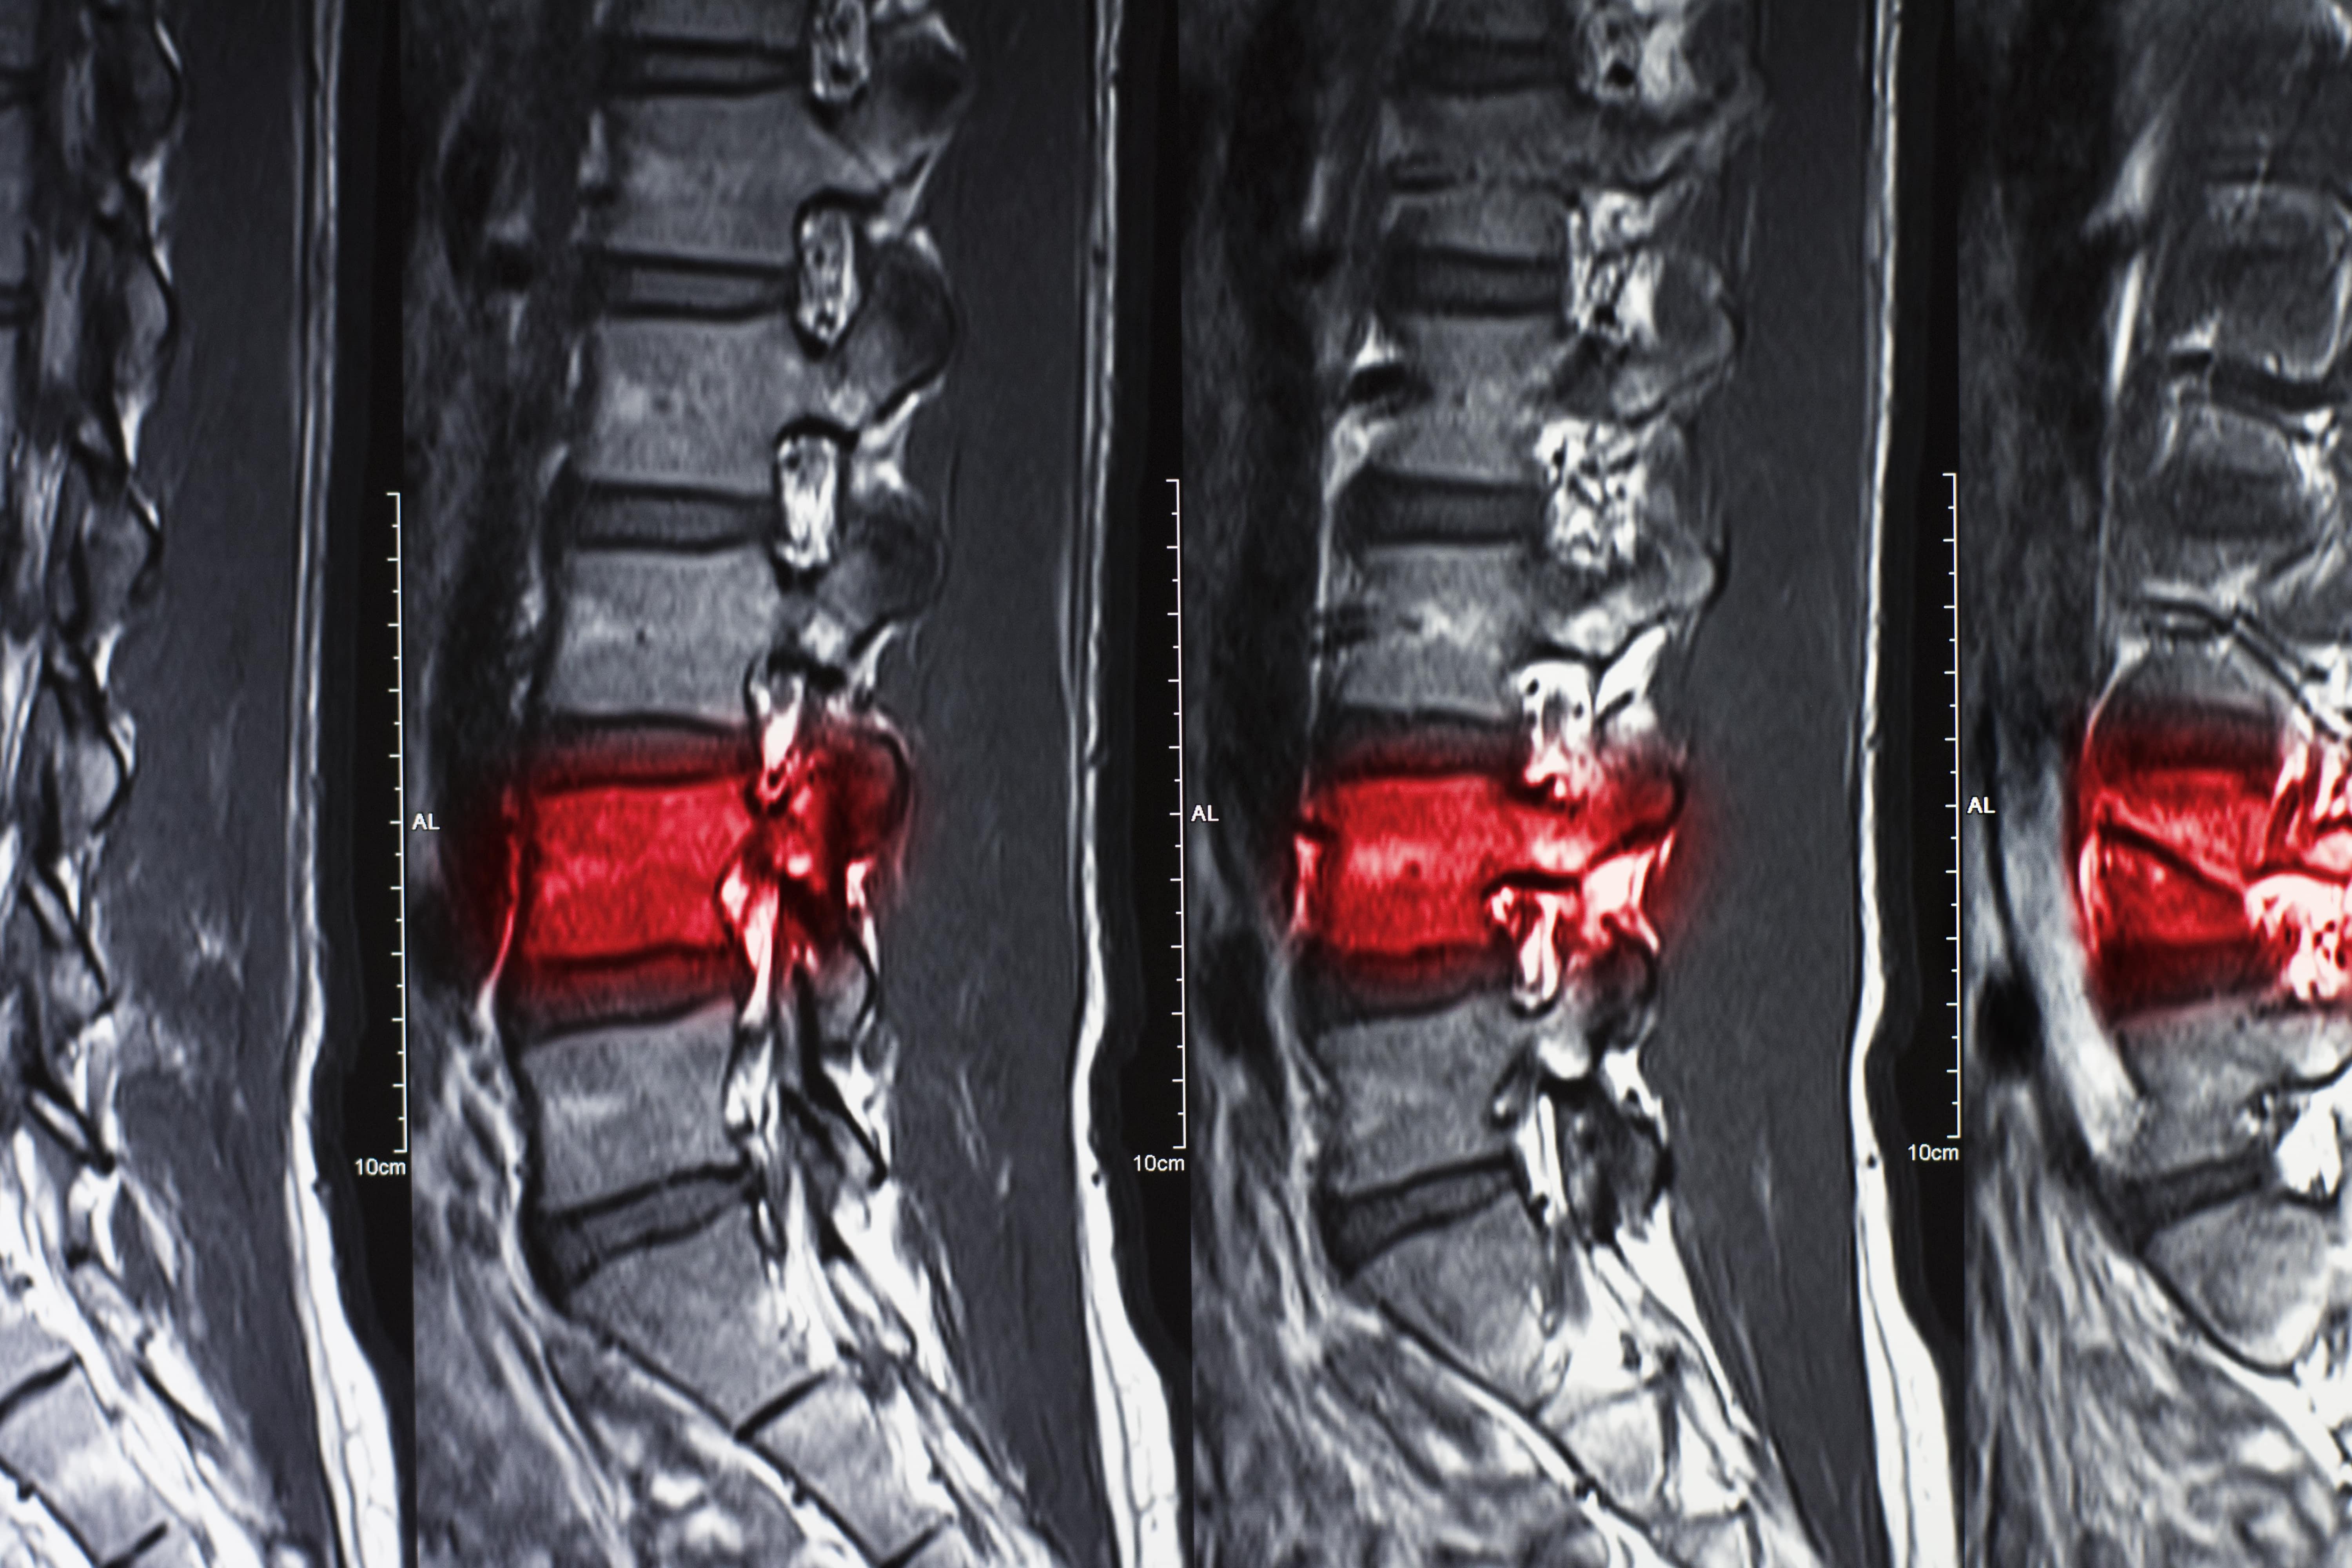

Thoracic spine surgery is a specialized procedure aimed at addressing conditions affecting the middle portion of the spine, known as the thoracic region. The thoracic spine consists of 12 vertebrae located in the upper and mid-back, and it plays a critical role in supporting the rib cage and protecting the spinal cord. Conditions such as herniated discs, fractures, spinal stenosis, or tumors in this region can cause severe pain, numbness, or weakness in the back, chest, and limbs. When non-surgical treatments fail to provide relief, thoracic spine surgery may be recommended to alleviate symptoms and improve function.

Thoracic spine surgery often involves advanced minimally invasive techniques, which help reduce muscle damage, minimize scarring, and shorten recovery times. Surgeons use sophisticated imaging technologies such as CT scans, MRI, and fluoroscopy to guide the surgery precisely. In certain cases, robotic-assisted surgery may also be employed to enhance precision and improve the overall outcomes of the procedure.